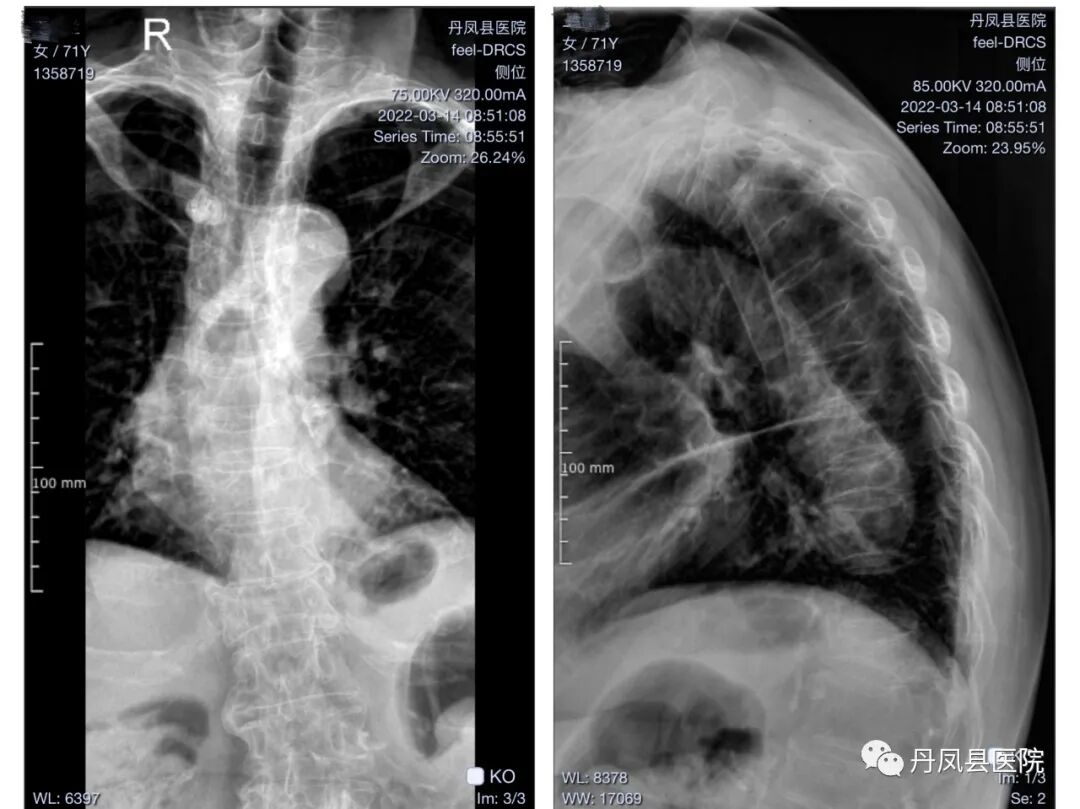

图为患者术后胸椎影像图片